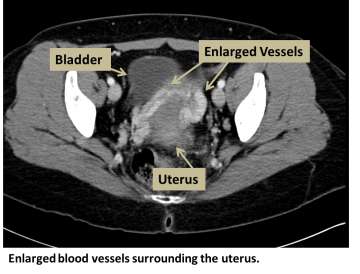

Pelvic congestion syndrome (PCS) is an abnormal enlargement of veins (varicose veins) in the pelvis, including around the ovaries. Normally, veins bring deoxygenated blood back to the heart, but when the blood cannot flow properly, blood builds up and causes veins to dilate. Disruption in blood flow can result from problems with or missing valves in the veins or compression from a tumor or other blood vessels. PCS can also occur because of pregnancy. PCS does not occur during menopause because women in menopause have less estrogen, and estrogen dilates veins. The enlarged veins in PCS are similar to other varicose veins that occur in the legs.

- CT scan